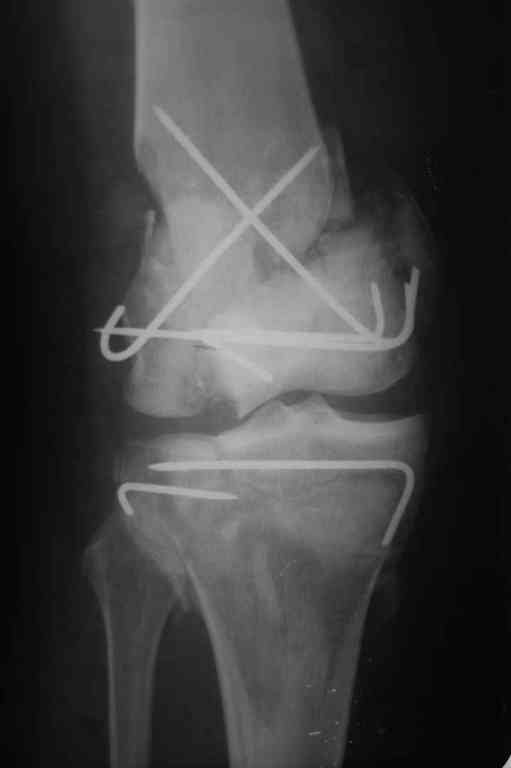

Re: Последствия открытого перелома дистального отдела бедра

Пожалуйста, снимки.